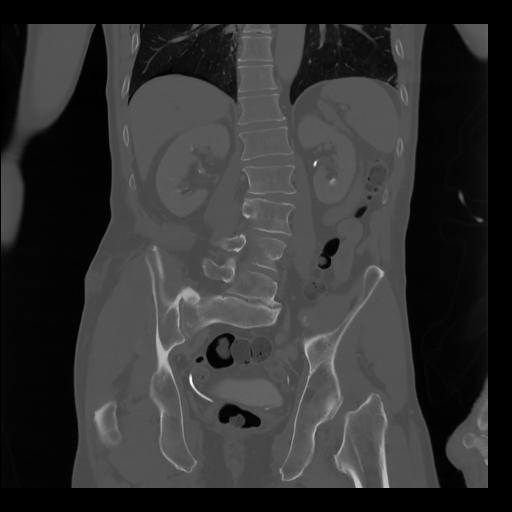

35 CUERPO,CE,Coronal,3.000,CUERPO,Coronal,